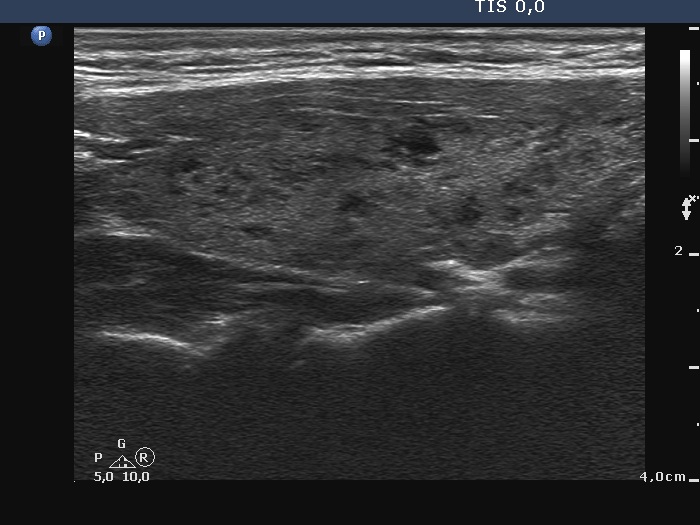

Right lobe, longitudinal scan

Right lobe, longitudinal scan. This is a typical presentation of Hashimoto's thyroiditis.